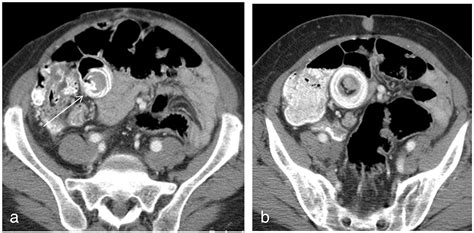

CT Scan Structural imaging of the abdomen Moderate (good for complications like obstruction)

The interpretation of a Meckel’s Diverticulum Scan requires expertise in nuclear medicine. A positive result is indicated by a “hot spot”—an area of increased radioactivity that appears in the lower abdomen during the imaging sequence. This “hot spot” corresponds to the area where the technetium-99m has accumulated in the gastric mucosa.

Advancements in Imaging Technology